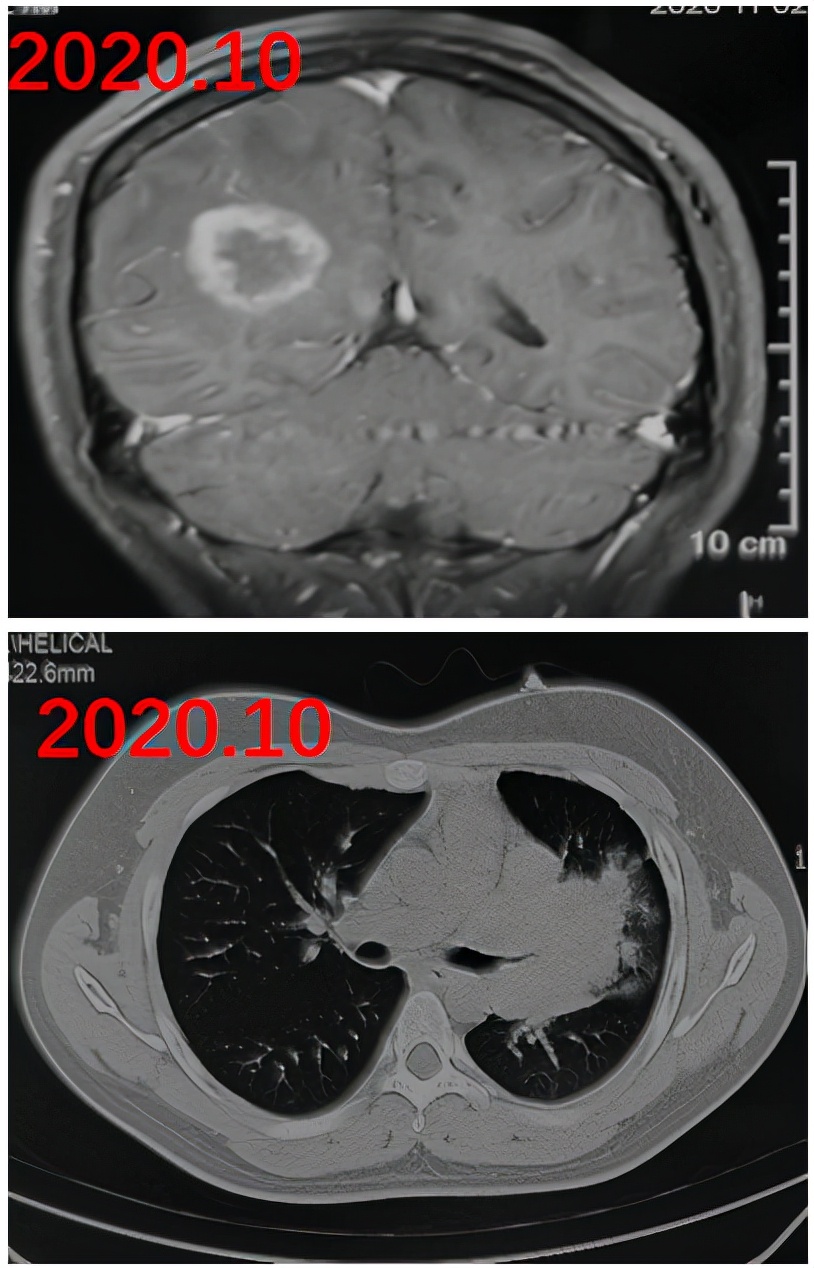

这是一位75岁的男性骨髓增生异常综合征(MDS)患者,化疗后出现发热咳嗽一个月,多种抗生素(泰能、替加环素、利奈唑胺) 以及伏立康唑治疗无效。

影像可见患者右下肺有较大的实变:

胸水是血性的,我们下了决心去穿刺,肺穿刺组织培养48小时发现根毛霉,病理也看到了丝状真菌: